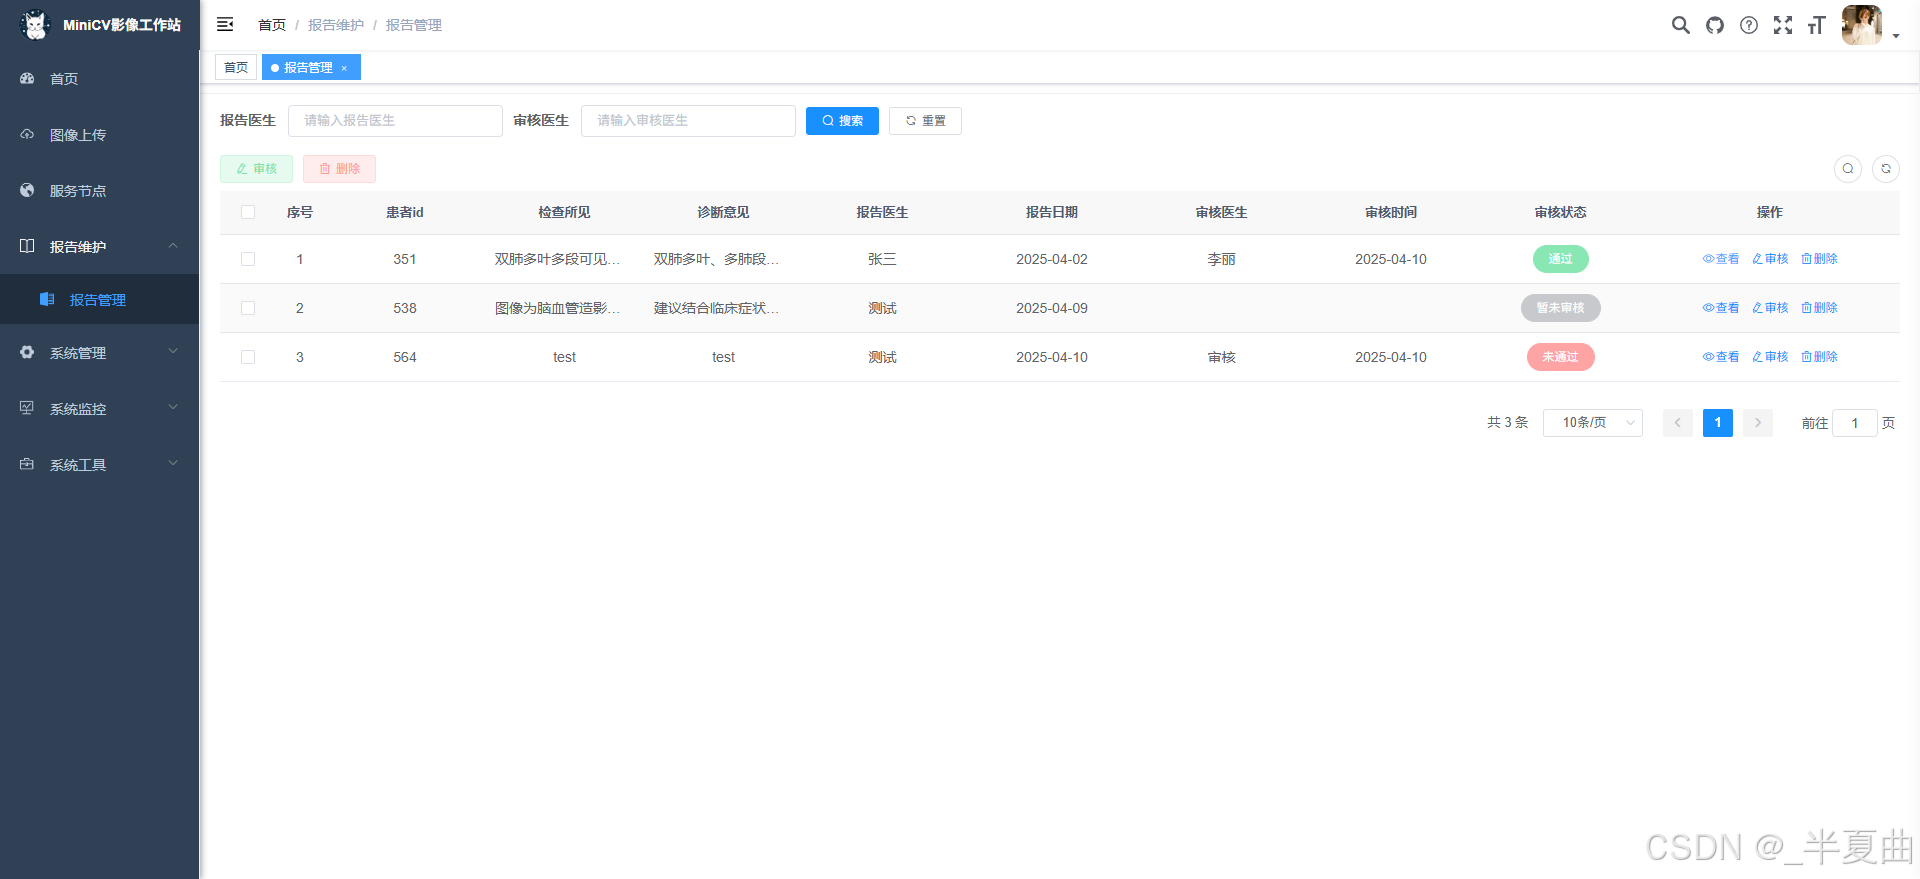

✅在线检查报告维护

报告管理: